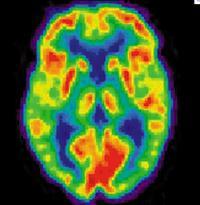

The campus will house large-scale facilities to produce positron emission tomography (PET) imaging agents. When injected into the body, these specialized radiopharmaceuticals, called biomarkers, detect and trace abnormal cellular functions that are associated with a variety of diseases. Visible using sophisticated imaging scanners, these biomarkers make it easier for physicians to non-invasively diagnose critical, life-threatening diseases in their earliest stages. They can also improve physicians’ ability to track the effectiveness of patient treatment plans.

State-of-the-art PET manufacturing facility: The center will house the latest technology in PET manufacturing, including dual cyclotrons, which can be used to produce large quantities of radioisotopes. It will also contain production facilities that allow for the simultaneous radiosynthesis of multiple imaging agents, for both commercial and research purposes.